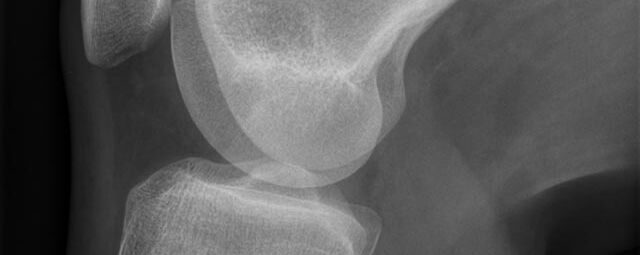

Konventionelles Röntgen

Der Begriff Röntgen, oder auch Röntgendiagnostik bezeichnet ein Verfahren in der Radiologie, bei dem von einer Röntgenröhre elektromagnetische Wellen (Röntgenstrahlen) durch die zu untersuchende Körperregion des Patienten gesendet werden. Je nach Dichte der Gewebeart des Körpers (z.B. Knochen oder Lunge) werden die Röntgenstrahlen im Körper unterschiedlich stark abgeschwächt. Ein digitaler Detektor empfängt dann die Röntgenstrahlen, die in abgeschwächter Form den Körper wieder verlassen haben. Daraus wird das Röntgenbild erzeugt.

Die zu untersuchenden Anteile des Körpers werden meistens

in 2 unterschiedlichen Projektionsebenen dargestellt.

In einigen Körperregionen sind spezielle Zielaufnahmen notwendig.